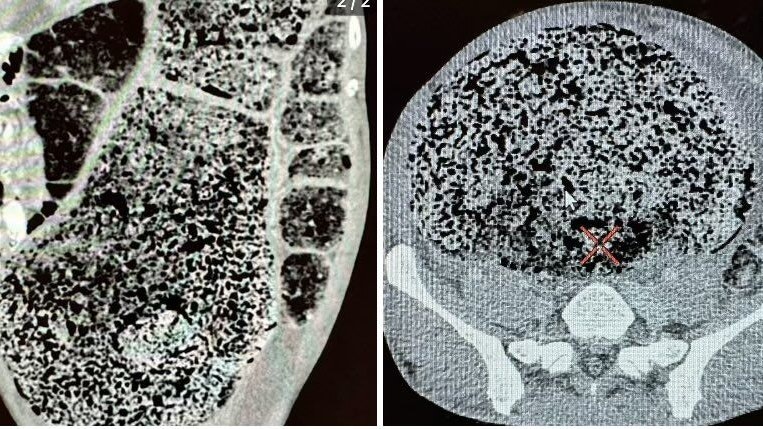

CT-Scans zeigten die große, körnige Masse, die im Körper des Mannes steckte.